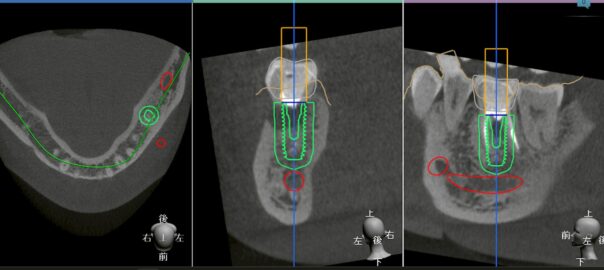

【インプラントの精度は本当に上がったのか?】サージカルガイドの利点と欠点を歯科医が解説

インプラント治療において「サージカルガイド」という言葉を耳にする機会が増えました。 デジタル技術の進歩により、より正確で低侵襲な治療が可能になった、それは事実です。 しかし、精度が上がった=安全になったとは単純に言い切れ … 続きを読む 【インプラントの精度は本当に上がったのか?】サージカルガイドの利点と欠点を歯科医が解説